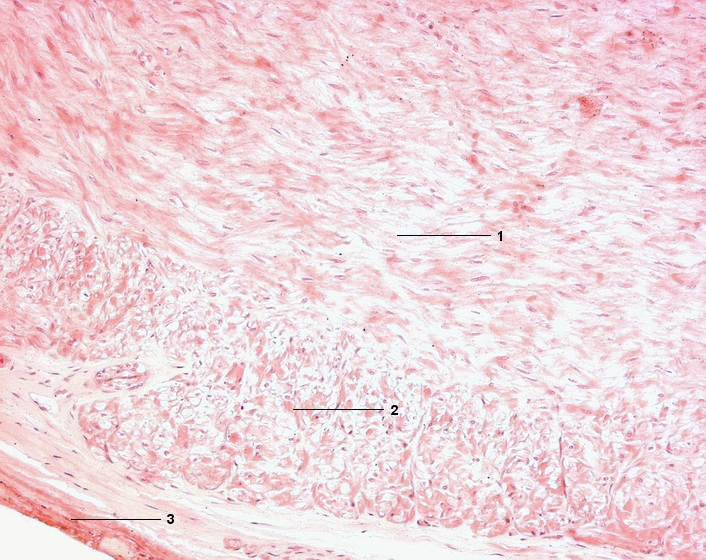

1 Tunica muscularis, mittlere Ringmuskelschicht

2 Äußere Längsmuskelschicht

3 Tunica adventitia